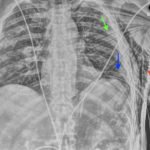

Plain film anteroposterior (AP) radiography of the chest shows left-sided subcutaneous emphysema (red arrow) with overlapping muscle striations of the pectoralis major (green arrow). After chest tube placement (blue arrow), AP chest radiography shows persistent left-sided subcutaneous emphysema (red arrow). CT of the chest shows pneumomediastinum (blue arrow), left apical pneumothorax (pink arrow), and subcutaneous emphysema (red arrow) at the level of T2. At the level of T6, rib fractures can be visualized on the CT (yellow arrow). At the level of T8, left sided pneumothorax is also seen (pink arrow) as the absence of lung tissue on CT.

In this patient, given the findings of multiple bilateral rib fractures, bilateral hemothorax/pneumothorax and multiple spine fractures, bilateral chest tubes were placed which had immediate output. The patient was admitted to surgical intensive care unit for chest tube management, pulmonary hygiene and further management of his other injuries.